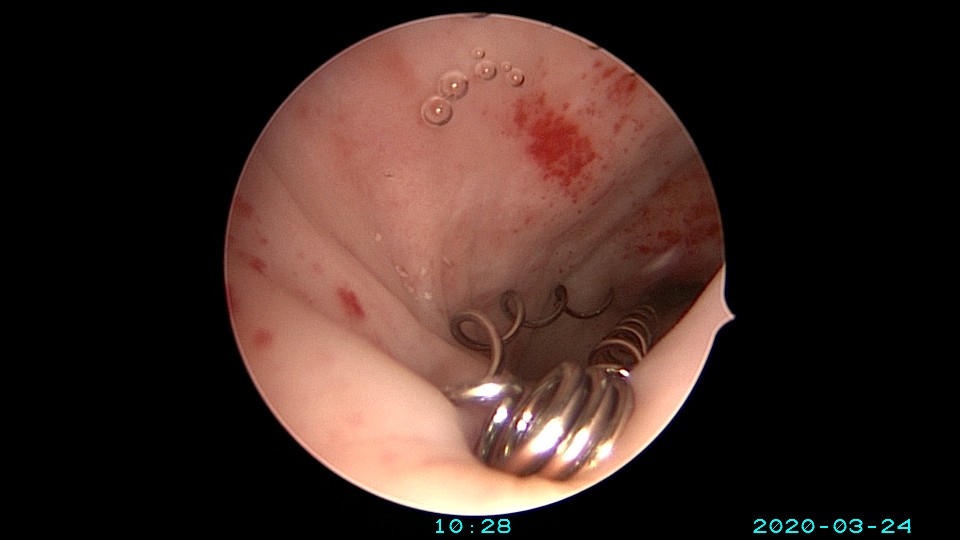

患者65岁,G1P1,顺产1次。安环30年,绝经10年。外阴白斑,阴道明显萎缩,无法置入扩阴器,阴道内镜方式找到宫颈外口,宫颈萎缩,穹隆几乎消失,无法夹持宫颈,宫颈管见多个息肉,宫颈内口狭窄坚硬,难以扩张。微型异物钳探查宫腔方向,用异物钳、微型剪刀扩大宫颈内口失败,改用双极电针切开宫颈内口,但镜子仍无法进入宫腔。用异物钳反复牵拉O型环至阴道内,中弯钳配合卵圆钳拉出节育环,环变形。有人问我何不用取环钩取环,这个病人探针和取环钩都无法发挥作用。